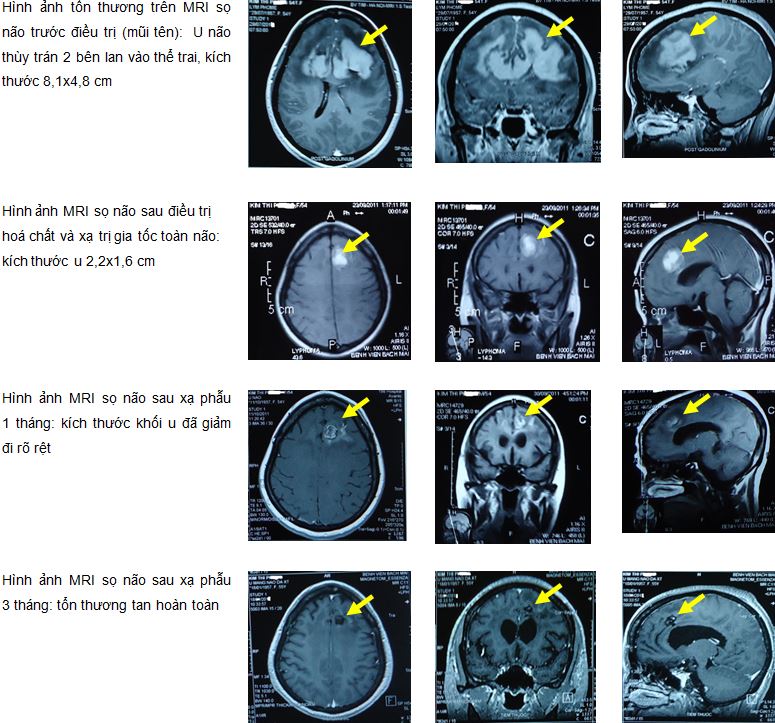

Bệnh sử: Bệnh nhân xuất hiện đau đầu dai dẳng mức độ nhẹ đến vừa nhiều tháng nay, điều trị nội khoa bằng thuốc giảm đau không khỏi. Khoảng 1 tháng trước khi vào viện bệnh nhân xuất hiện đau đầu tăng dần, kèm theo đôi lúc có buồn nôn, nôn, trí nhớ giảm dần, không liệt vận động, không sốt. Bệnh nhân đi khám và được chỉ định chụp phim cộng hưởng từ (MRI- Magnetic resonance imaging) sọ não thấy: hình ảnh tổn thương nhu mô não thuỳ trán hai bên phát triển qua thể trai là khối tín hiệu tổ chức đặc, kích thước 8,1 x 4,8 cm, giảm tín hiệu trên T1W, đồng tín hiệu trên T2W, tăng nhẹ tín hiệu trên phim Diffusion, tổn thương ngấm thuốc mạnh sau tiêm thuốc đối quang từ. Khối phát triển hai bên thuỳ trán, lan vào sừng trán não thất bên hai bên, bờ không đều, giới hạn không rõ, phù não rộng xung quanh. Kết luận: hình ảnh u não thuỳ trán hai bên nghĩ đến glioblastoma multiforme phân biệt với lymphoma.

Hình 1. Hình ảnh MRI sọ não trước điều trị: U não thùy trán 2 bên lan vào thể trai, kích thước 8,1x4,8 cm (mũi tên)